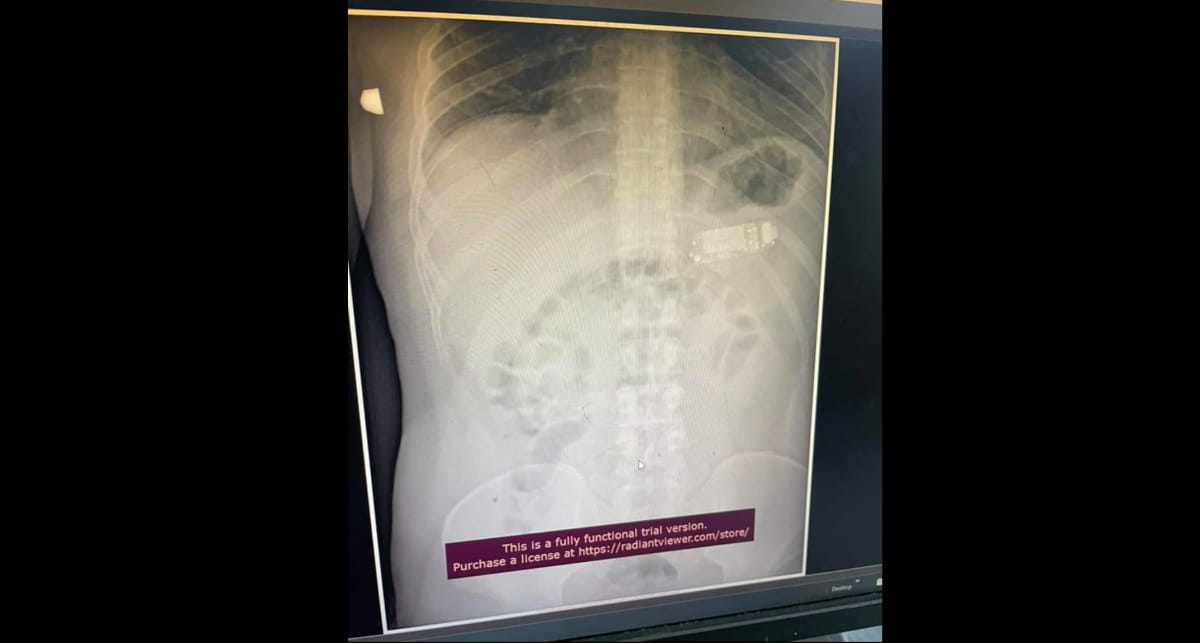

У Косові 33-річний чоловік проковтнув мобільний телефон Nokia 3310, який представили понад 20 років тому. Про це повідомляє "Дивогляд" із посиланням на Metro.

У постраждалого гаджет застряг у животі, але телефон був занадто великий і шлунок не зміг його перетравити. Паралельно з цим з акумулятора почали витікати отруйні речовини.

У підсумку довелося втрутитися лікарям, які змогли на операційному столі, не розрізаючи шлунок, вийняти телефон частинами. На щастя, операцію провели без ускладнень.